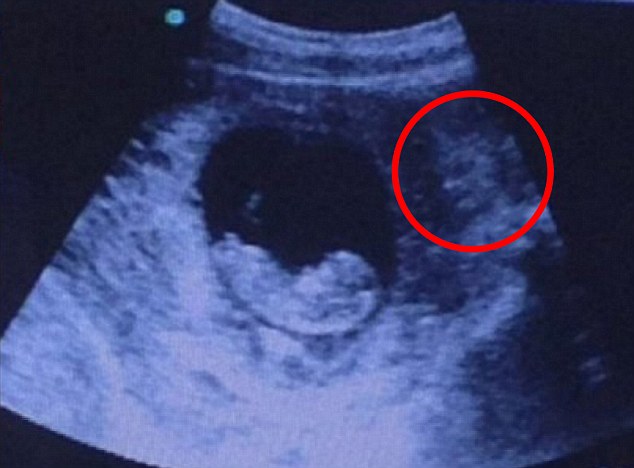

2月大胎儿超声波照片酷似被“恶魔”注视

据英国《每日邮报》1月3日报道,日前,一位网友在网络上晒出一张2月大胎儿的超声波照片,看上去酷似一个恶魔正注视着母亲子宫中的胎儿,让人毛骨悚然。

照片中,胎儿已初具人形,而超声波影像整体看上去仿佛是一个阴森恐怖的“恶魔”正在母亲子宫外注视着这个胎儿。“恶魔”长着黑色大眼睛,头上长着喇叭状的标记,来势汹汹。

该照片被传到网上后,引起各路网友一片热议,两天之内浏览量就已经超过100万次,他们纷纷用千奇百怪的方式描述这张照片。有人称一个“恶魔”正不怀好意地看着胎儿,有人称自己在胎儿左右各看到一张“恶魔”的脸,有人称这名胎儿是一个“哭泣的天使”,还也有人称自己看到的是一条友好的“美人鱼”。